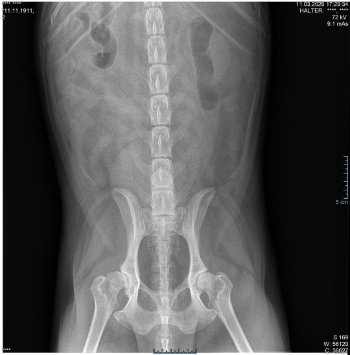

Den Er ist erst 6 J. geworden u.benötigt eine neue Hüfte .Bis dahin bekommt er Spritzen gegen die Schmerzen und Entzündungen.Kann nur sehr kurze Strecken gehen noch und ist ein ganz großer Rückhalt für meinen Bruder der an Asbergersyndrom (leichte Form)leidet.